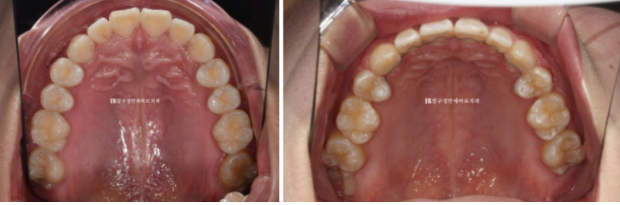

치아는 가지런한 편이고 어금니 교합도 좋지만 앞니 뻗침이 보입니다.

치료계획은 작은 어금니 4개를 발치하고 돌출입을 확실히 개선하기로 했습니다.

클리피씨 장치를 선택하셨고 바로 교정 시작했습니다.